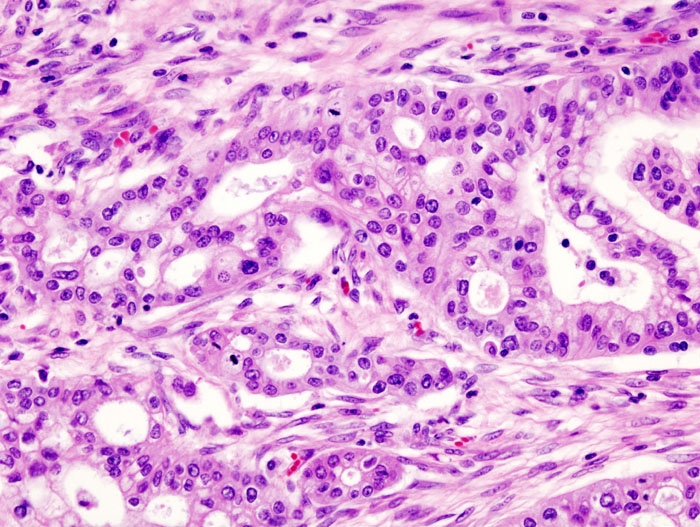

6. 췌장암 (Pancreatic adenocarcinoma)

췌장암은 대부분이 췌장 외분비관에서 기원하는 침윤성 선암

• 사망률이 매우 높고 예후가 불량한 악성 종양

2) 병리학적 특징

60%는 췌장의 머리에 발생 → 조기 담도 폐쇄 및 황달 유발

• 섬유모세포반응(demosplastic stroma) 동반하는 선암

• perineural invasion, 림프관 침윤 매우 흔함

Pancreatic adenocarcinoma, Wikimedia Commons